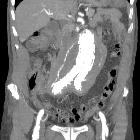

CT

Retroperitoneal fibrosis is visible as a soft tissue density mass located around the aorta and iliac arteries. Classically, it develops around the aortic bifurcation and spreads upwards where it can envelop the renal hila. It encases but does not invade or stenose the ureters or vessels. However, ureteric obstruction and venous thromboses can occur.

In early or active stages, variable enhancement can be seen with intravenous contrast while no enhancement may be seen in the quiescent disease.